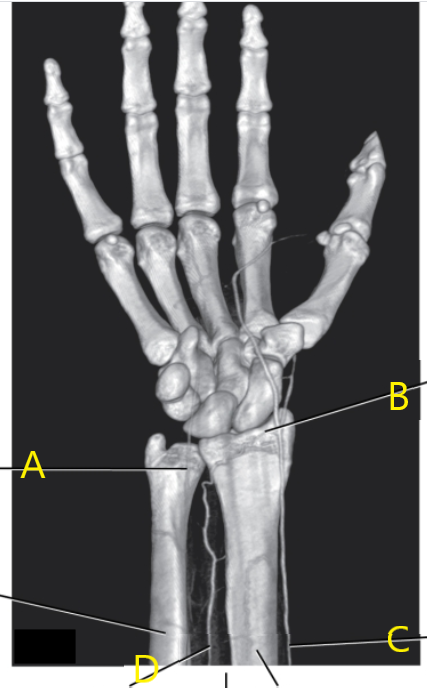

What is # 3 ?

Radius

What is letter A arrow pointing to ?

Ulnar artery

What is letter e ?

Hook of the hamate

Scaphoid

What ligamentous structure spans the wrist to create an enclosure for the passage of tendons?

Flexor retinaculum

What is # 2 ?

Lunate

What is letter d ?

Triangular fibrocartilage complex

What is letter c ?

Coronoid process